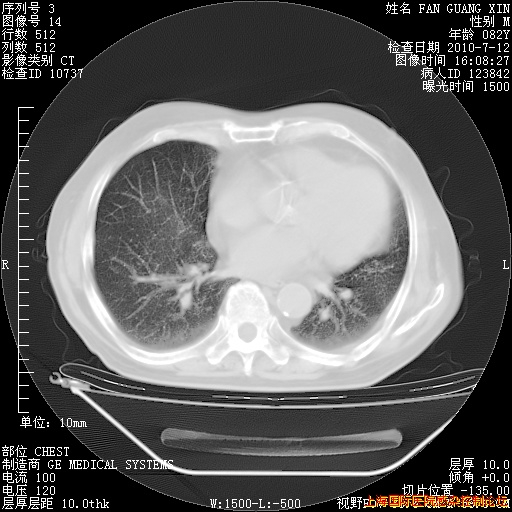

补发6月12日肺部CT肺窗

6月12日肺窗